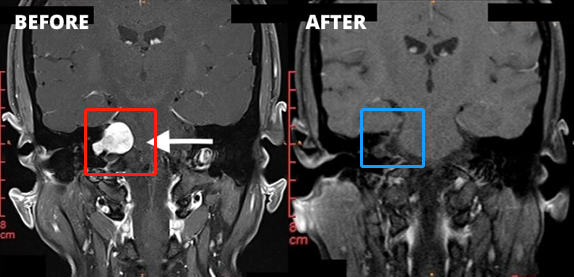

1、左側(cè)圖示(紅色)患者術(shù)前核磁:右側(cè)橋腦小腦角區(qū)見一類圓形占位性病變,邊界清楚,T2WI高信號,其內(nèi)信號欠均勻,增強(qiáng)掃描后病變呈明顯強(qiáng)化,同側(cè)橋腦小腦角池?cái)U(kuò)大,內(nèi)聽道擴(kuò)大,四腦室輕微受壓。

2、右側(cè)圖示(藍(lán)色)患者術(shù)后核磁:術(shù)后腫瘤切除干凈,做到了全切全切,核磁未見占位性病變。與術(shù)前對比明顯可見腫瘤完整切除,較大限度減少復(fù)發(fā)可能。

3、患者術(shù)前情況:右耳耳鳴3個(gè)多月,聽力下降,頭昏頭痛加重。面肌抽搐、舌頭、牙齦和臉有麻木感覺,無法正常生活。

4、患者術(shù)后情況:術(shù)后1周出院,術(shù)后2周面神經(jīng)功能House-Brackman分級1級。面神經(jīng)保留,沒有面癱,聽力保留。術(shù)后9個(gè)月隨訪,恢復(fù)很好,能夠正常生活。

5、手術(shù)總結(jié):聽神經(jīng)瘤切除手術(shù)規(guī)模較大的挑戰(zhàn)是確定90%以上切除率的同時(shí),既不損傷聽神經(jīng)、聽力,也不損傷面神經(jīng),不會(huì)發(fā)生面癱。以上腫瘤全切術(shù)由巴特朗菲教授操作,術(shù)后聽力保留較好,且無面癱。這樣的手術(shù)效果堪稱,這樣的技術(shù)手法和水平即使是國際神經(jīng)外科醫(yī)院案例中也可以作為教科書級別的案例。